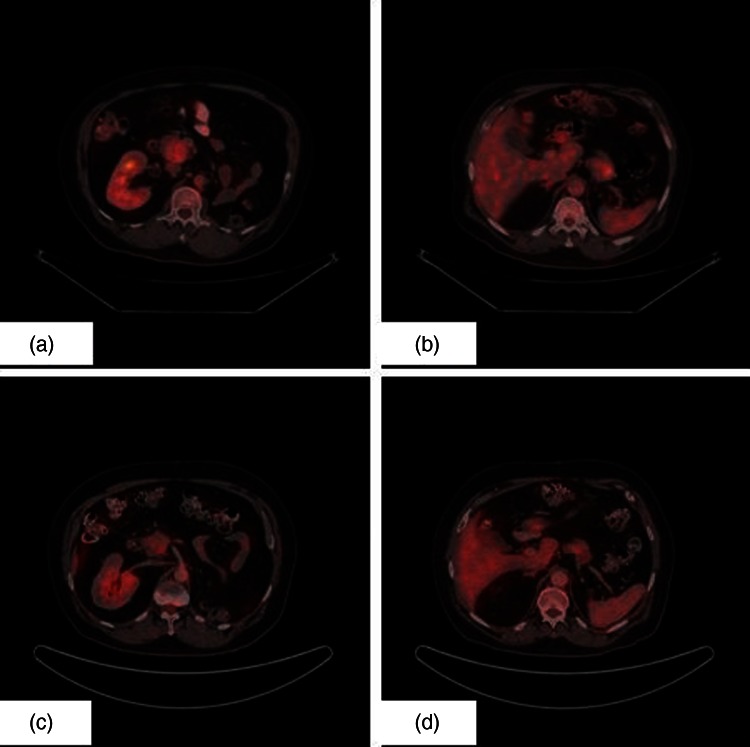

Ultrasonography of abdomen showed a lesion in the head of the pancreas. A CECT of the abdomen revealed a mass in the head of the pancreas of size 4.0 cm×3.0 cm. Biochemical investigations were within normal limits. Carbohydrate antigen 19-9 level was normal. Positron emission tomography (PET) scan revealed two soft tissue mass lesions in the pancreas: one in the head region (4.0 cm×3.0 cm) (standard uptake value (SUV) 4.1) and the other in the tail of pancreas (3.3 cm×3.1 cm) (SUV 4.8) (figure 1A,B). Fine needle aspiration showed clusters of malignant cells which are moderately pleomorphic having round to oval nuclei, coarse chromatin and abundant clear cytoplasm suggestive of metastatic RCC (figure 2).

Figure 1.

(A). Positron emission tomography (PET) image showing metastatic lesion in head of pancreas. (B). PET image showing metastatic lesion in tail of pancreas. (C). Postsunitinib PET image showing response in the metastatic lesion in head of pancreas. (D). Postsunitinib PET image showing response in the metastatic lesion in tail of pancreas.

After three cycles of oral sunitinib, he again underwent interval PET scan for response assessment and the metastatic lesions had significant decrease in size and SUV uptake (figure 1C,D). He tolerated oral sunitinib well with no significant haematological and biochemical toxicity. He is presently on the fifth cycle of oral sunitinib and is doing well with clinically asymptomatic status.